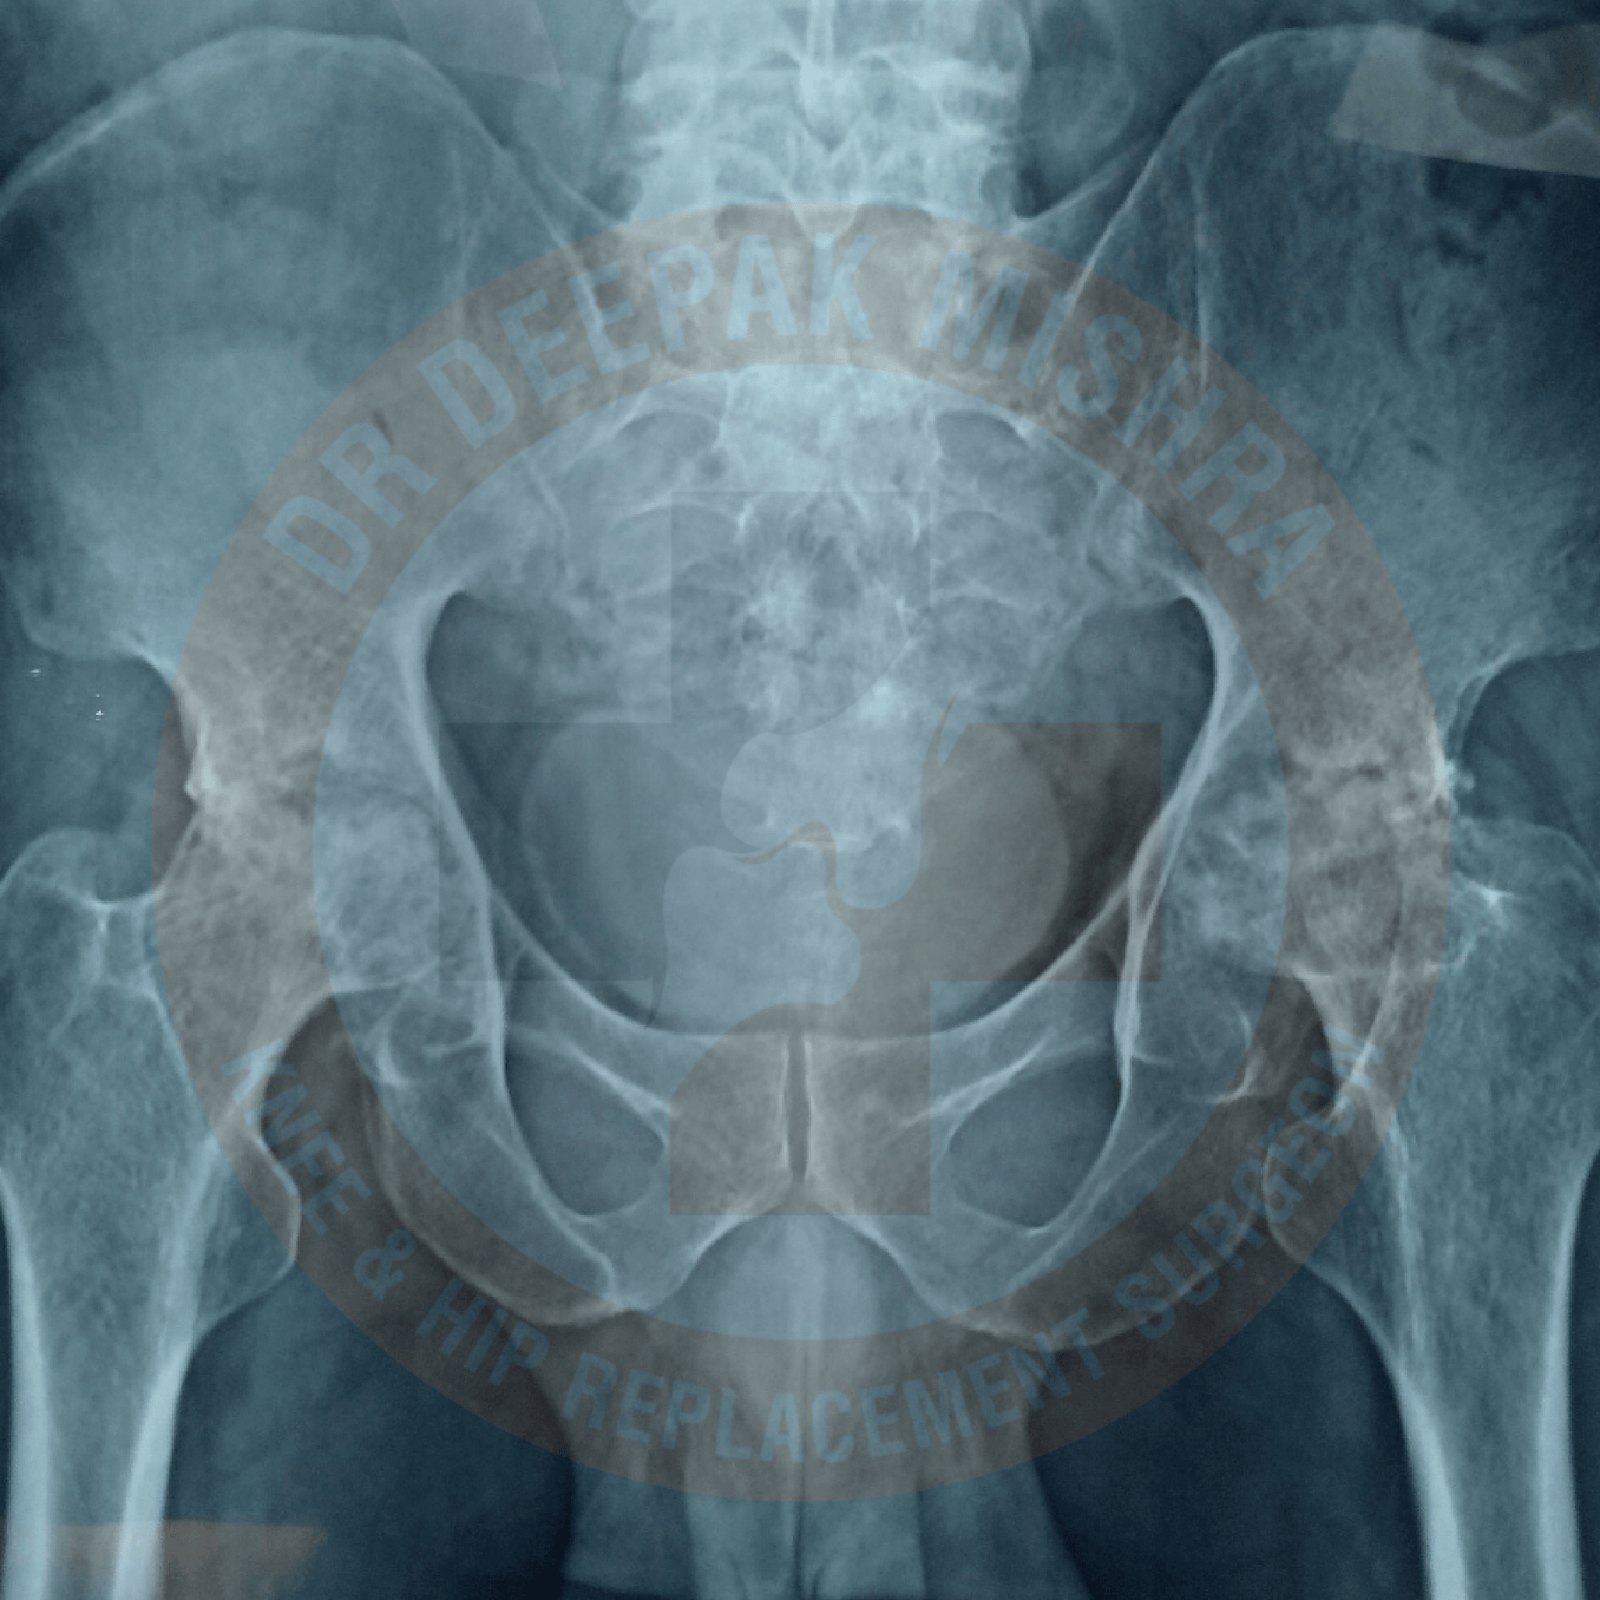

Arthritis in hip joint can lead to difficulty in walking and performing daily chores of life. Primary arthritis of Hip joint is uncommon in Asian, Hispanic or Black populations. Mostly, patients in these ethnicities suffer with secondary arthritis due to trauma, dysplasia of hip, avascular necrosis, inflammatory arthritis or infection in the hip joint. Due to the secondary nature of the disease, they appear at an earlier age, maybe as early as the second decade of their life. This early onset poses increased morbidity for the patient and surgical challenges for the orthopaedic surgeon. The inability to perform normal activities at young age produces feelings of hopelessness in patient and worsens physical and financial output. Due to lack of awareness and at times remote access to the healthcare system causes further delays in seeking medical advice from an orthopaedic surgeon.

It usually occurs due to trauma to the hip joint, avascular necrosis (lack of blood supply to ball of the femur), infections (tuberculosis/septic), childhood hip problems (congenital hip dislocation, Perthe’s disease, slipped capital femoral epiphysis, etc) and inflammatory arthritis like rheumatoid arthritis or ankylosing spondylitis.

Due to damaged hip, patients experience pain in day-to-day activities. They have difficulty in sitting crossed leg, squatting or using stairs. As disease progresses with time, the deformities appear in hip joint leading to reduced mobility and subsequently these patients become bedridden. Increasing deformity also produces changes in spine and knee joints, if not treated on time. Few patients presents with complaints of not able to perform marital obligations.